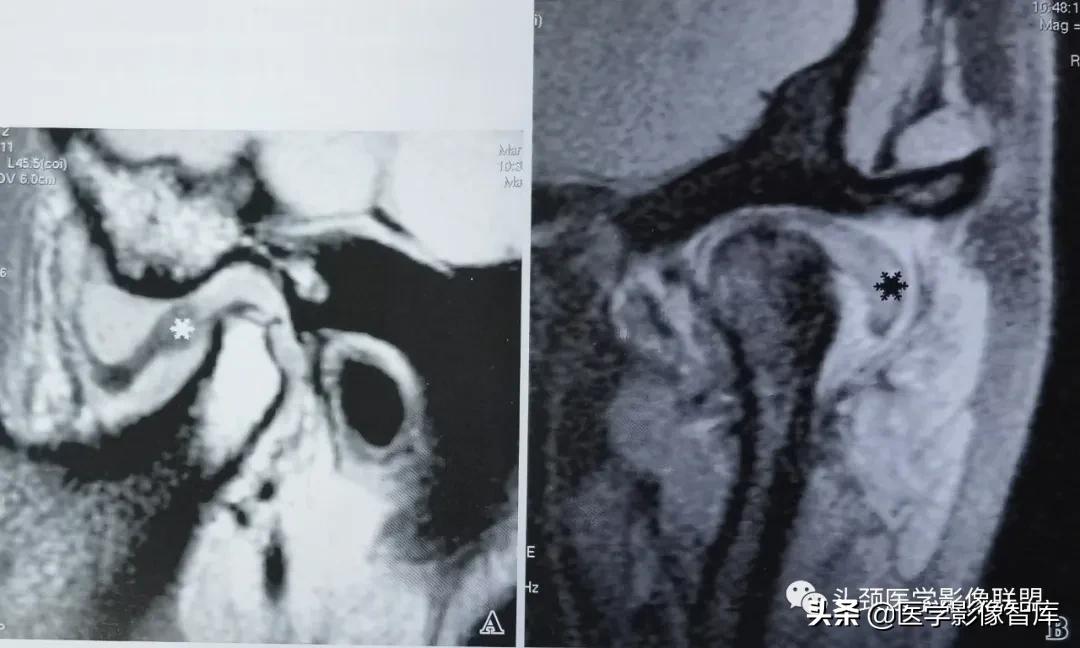

图1 可复性关节盘前移

A. 矢状面闭口PDWI示:关节盘后带(黑星)位于下颌髁突前方;B.矢状面开口T2WI示:盘 一 髁关系恢复正常。关节上腔内有少量积液。

可复性盘前移的临床主要表现为弹响。它是指闭口位时关节盘后带位置位于下颌髁突横嵴顶的前方;张口时,髁突向前移动撞击关节盘后带发生弹响,关节盘向后反跳,随后恢复到正常盘一髁关系。可复性盘前移位的MRI表现特点为:矢状面闭口位上 (图1A) ,低信号的关节盘位于下颌髁突横嵴顶12点位的前方,关节盘双板区与后带之间的界限较为模糊;矢状面张口位上 (图1B) ,盘一髁关系恢复正常。即下颌髁突横嵴顶12点位的上方是关节盘中间带,关节盘后带位于下颌髁突的后方。大多数情况下,可复性盘前移位时的关节盘外形少有形态上的异常改变。不完全性关节盘移位多为可复性盘移位。